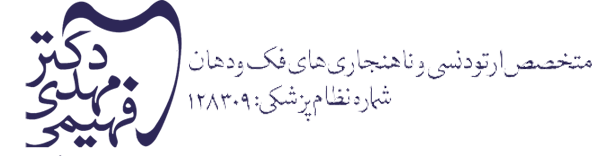

بافت متورم معمولاً در نتیجه بهداشت نامناسب دهان ایجاد می شود. این بافت اضافی نه تنها بد به نظر می رسد، بلکه روی مینای دندان نیز رشد می کند و حذف پلاک را در آینده دشوارتر می کند. به طور کلی، یک متخصص ارتودنسی ممکن است استفاده از چنین درمانی را برای ایجاد احساس راحتی بیشتر در هنگام برداشتن ساختارهای مؤثر بر دندان ها و لثه ها و همچنین خلاص شدن از شر بافت متورم، انتخاب کند که می تواند برداشتن پلاک را آسان تر کند. یکی از مواردی که استفاده از لیزر به طور چشمگیری زمان درمان را کوتاه می کند، برداشتن بافت لثه هنگام اتصال بریس است. بیماران همچنین از افزایش توانایی در حفظ بهداشت دهان و دندان سود می برند. یکی دیگر از دلایل استفاده از لیزر در ارتودنسی، برداشتن بافت متورم است. با کاهش تورم لثه ها، ارتودنتیست شما می تواند به مینای زیرین دسترسی بهتری داشته باشد و تمیز کردن کامل تر و گسترده تر را انجام دهد. بافت های متورم می توانند باعث درد شوند و به ظاهر ناسالم لثه ها کمک کنند.

روش های مرسوم برای حرکت و صاف کردن دندان ها نیاز به استفاده از بریس دارند. برای اینکه ارتودنتیست شما بتواند دندان ها را حرکت دهد، باید بتواند بریس ها را به هر کدام از دندان ها بچسباند. قبل از اینکه بتوان بریس ها را به سطح هر دندان وصل کرد، سطح باید تمیز و عاری از انسداد باشد. در برخی موارد سطح دندان توسط بافت لثه پنهان می شود. پنجمین استفاده از لیزر در ارتودنسی همانی است که در واقع زمان درمان را کوتاه می کند. با برداشتن بافت با استفاده از لیزر، می توان مدت زمان قبل از اعمال بریس را کاهش داد. مواقعی وجود دارند که سطح دندان به طور کامل یا تا حدی با بافت لثه پوشانده می شود. این ممکن است به این دلیل باشد که دندان نهفته است، یا ممکن است به این دلیل باشد که دندان کاملاً در نیامده است. اگر دندان نهفته دارید، یا دندانی دارید که تا آخر نیامده است، ممکن است نیاز به تکمیل این روش داشته باشید. به هر دلیلی، برداشتن بافت با استفاده از لیزر به منظور قرار دادن زود هنگام براکت، می تواند شش ماه تا یک سال از زمان انتظار مورد نیاز برای قرار دادن بریس ها طول بکشد. در این صورت استفاده از لیزر می تواند زمان درمان شما را به شدت کاهش دهد.

در صورت امکان، متخصص ارتودنسی قصد دارد با استفاده از آخرین تکنولوژی و روش های درمانی موجود، درمان سریع ارتودنسی را ارائه دهد. لیزرها اغلب برای کاهش التهاب مرتبط با بیماری های مختلف مانند آفت ها و سایر زخم ها استفاده می شوند. در طول درمان، متخصصین ارتودنسی قادرند لیزر را در فاصله ایمن از ناحیه آسیب دیده برای حساسیت زدایی از زخم نگه دارند. این روش را می توان در موقعیت های مختلفی که تورم و التهاب مانع بهبودی می شود، استفاده کرد. نتیجه این است که این ناحیه حساسیت زدایی شده و میزان بهبودی افزایش می یابد.